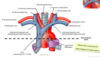

What structures are shown?

Explain what you can see from posterior- middle- anterior

Explain what is seen inferiorly

What is the ligamentous connection between the inferior most structure and middle structure?

Most posterior structure- trachea, bifurcation into L and R main bronchi.

Most anterior is the superior vena cava, receiving the R and L brachiocephalic veins. The R and L brachiocephalic veins receive from the R and L internal jugular vein.

Middle structure - Arch of aorta, on R side brachiocephalic trunk which splits into the R subclavian and R common carotid. Splits into the L internal carotid and L subclavian.

Inferior stucture is the pulmonary trunk.

Ligamentous connection between the aorta and pulmonary trunk is called the ductus arteriosus. It fuses soon after birth- open in utero to bypass the deoxygenated blood past the lungs and straight into the aorta.